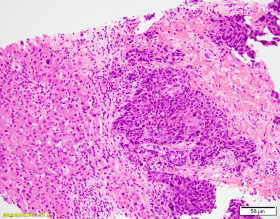

Patient is a 60-year-old male with a “bladder tumor.” Multiple nodules were present in the lung, liver and pelvic lymph nodes. A CT guided biopsy was performed, targeting the hepatic nodules. P40, synaptophysin and chromogranin are negative. MSI studies show loss of MLH1 and PMS2, with retained MSH2 and MSH6.

Picture1 WIN 20201023 14 55 38 ProWIN 20201023 14 56 49 Pro 2020-10-26T17:46:01Z

The patient has metastatic prostate cancer. Immunohistochemical stains are supportive for this diagnosis. NXK3 .1 is helpful in distinguishing poorly differentiated prostatic carcinoma from urothelial. NKX3.1 is a more sensitive and specific than PSAP. Aberrant staining of GATA 3 can be seen in subset set of prostatic carcinomas.  This potential pitfall that may be avoided with more specific and sensitive markers for prostate cancer. MSI loss may be seen in patients with prostatic cancer, however currently there is no increased risk in patients with a family history of prostatic cancer.